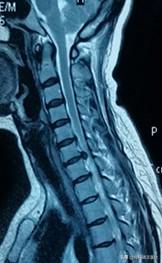

頚椎症の診断には、MRIなどの頚椎病変の画像変化があり、同時にそれに対応する臨床症状が伴っていなければならず、どちらか一方が欠けても診断がつかない。一つの項目だけで診断を下すことはできない。

神経原性頚椎症は主に頚椎の変性、頚部神経根の蓄積を指し、頚部神経根の神経支配領域の感覚障害と運動障害として現れ、好ましくは頚椎5-6、頚椎6-7椎間で、主な症状は頚部と肩の痛み、上肢の片側の持続的または断続的な痛みやしびれ、頚部の活動は咳によって悪化し、上肢の患側は重苦しさ、脱力感があり、物体が落下しているように見える。